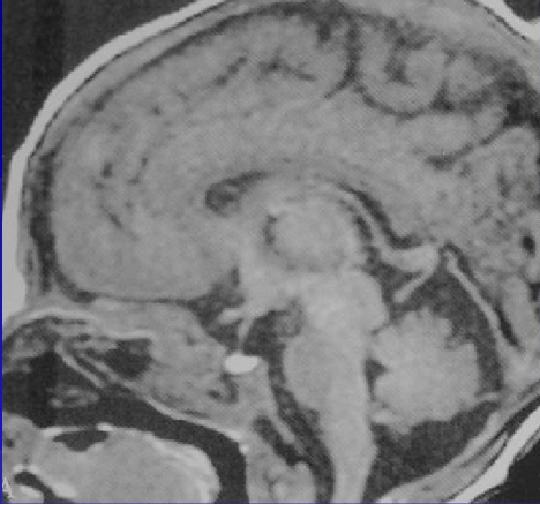

胎儿成像

垂体成像